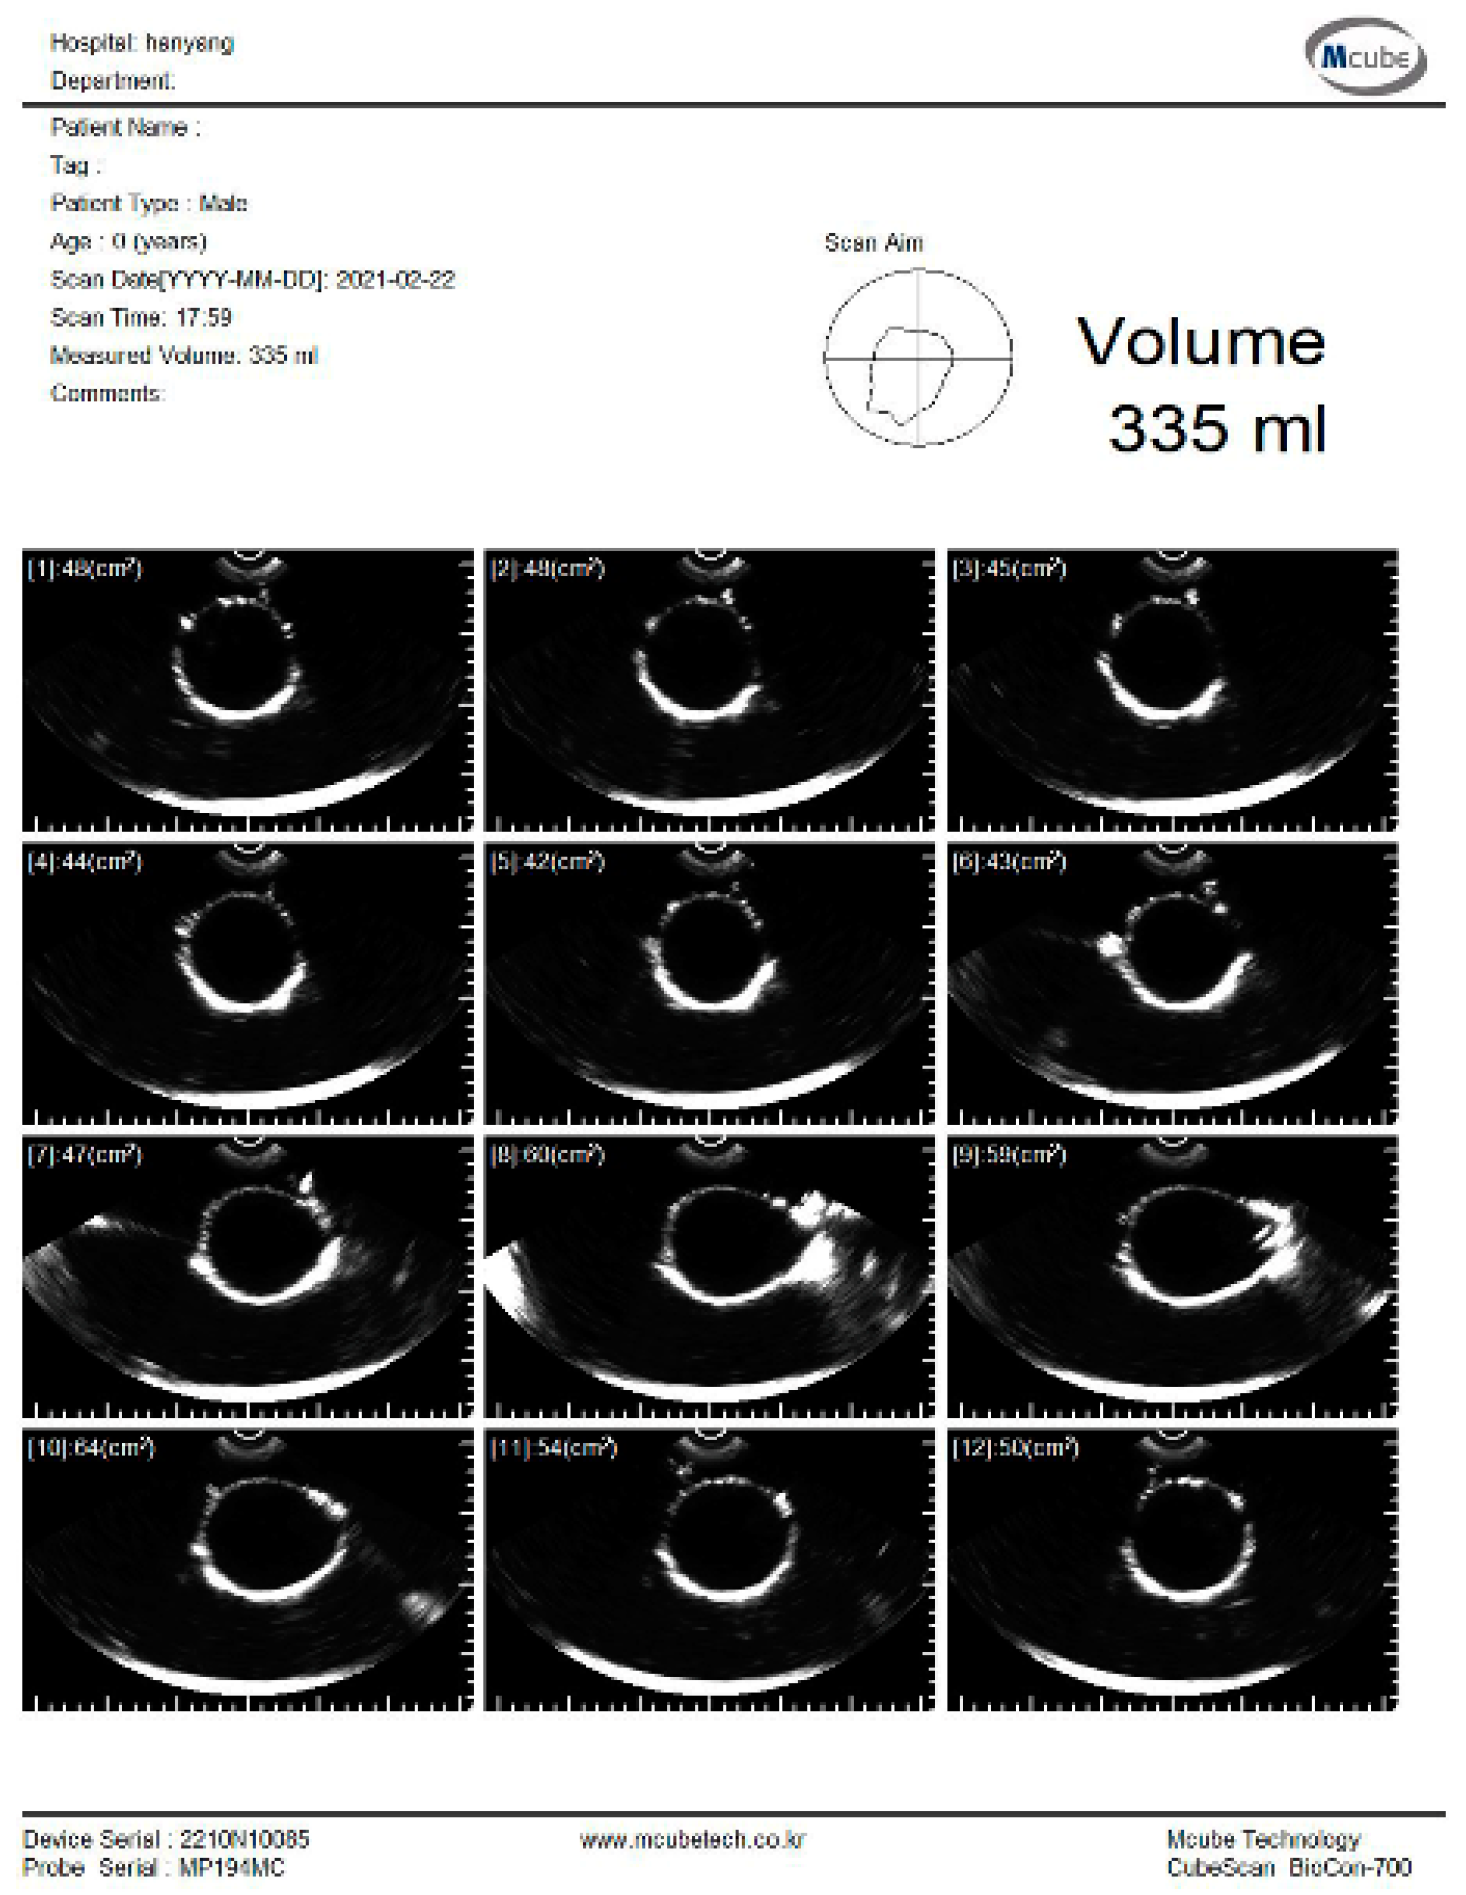

The experiment was conducted to estimate the volume using the pig bladder to verify the feasibility of the system. Whenever 50 mL of water was injected, the bladder volume was measured using a commercial bladder scanner (BioCon-700, MCUBETCH, Seoul, Korea). The working frequency of BioCon-700 is 2.6 MHz. Based on the manufacturer’s specification, the accuracy of volume estimation is ± 15%, when the target volume is greater than 100 mL (or ±15 mL on volumes less than 100 mL). Immediately after the commercial equipment measurement, 25 channel data were obtained using the fabricated device. The commercial equipment provided B-mode images and a volume estimation value of the pig bladder as shown in Figure 8. All measurements, which are performed with the commercial equipment, are in the reference images as shown in subfigures (a) in Figures S1–S7.

Figure 8.

B-mode images and estimated volume value of the pig bladder filled with 300 mL of water.